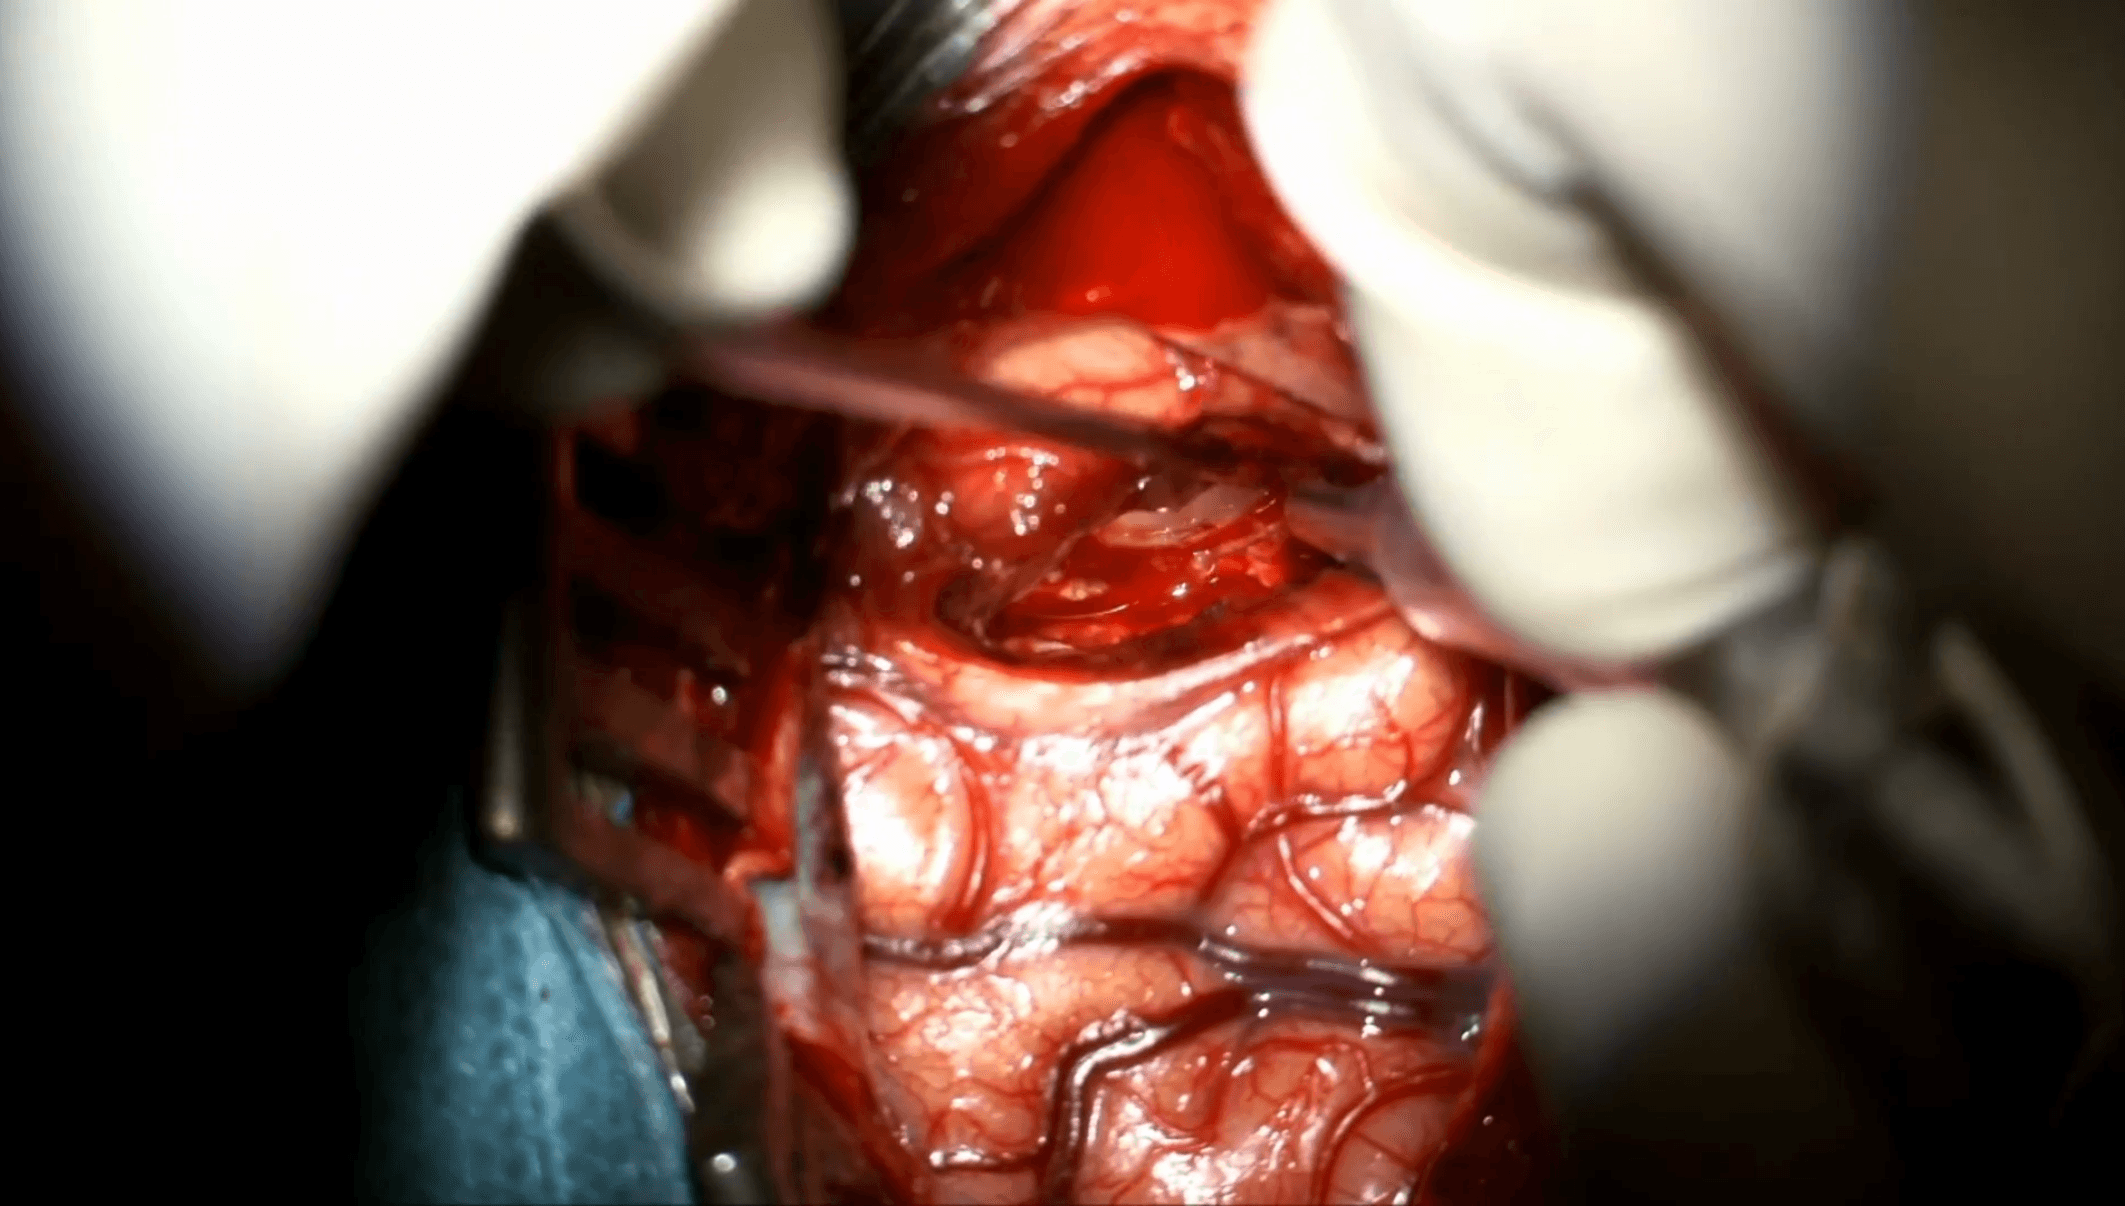

La cirugía completa de amigdalohipocampectomía selectiva transcortical realizada por el Dr. José Manuel Garbizu, del Hospital Universitario Gregorio Marañón (Madrid, España), puede verse en la app de cirugías online SurgSchool. En este caso se interviene a una paciente de 39 años, diestra, con epilepsia del lóbulo temporal fármaco-resistente secundaria a esclerosis mesial izquierda.

El abordaje transcortical se efectúa mediante corticectomía de aproximadamente 2 cm en el giro temporal medio, a nivel del labio inferior del surco temporal superior. Esta trayectoria ofrece acceso directo al asta temporal minimizando retracción excesiva y evitando disección transilviana.

Tras disección subpial se penetra en el asta temporal. La exposición amplia de cabeza y cuerpo del hipocampo se obtiene entre el surco ventricular lateral, la fisura coroidea y el receso uncal anterior.

Un retractor suave permite visión continua del hipocampo sin compresión prolongada.

La resección comienza con el giro parahipocampal en técnica subpial, progresando desde el surco ventricular lateral hacia el subiculum y el surco hipocampal. Este plano subpial protege estructuras vasculares profundas y limita sangrado.

La pieza principal se desancla mediante coagulación y sección de vasos hipocampales en el surco hipocampal. El control vascular meticuloso evita sangrado profundo en cavidad ventricular.

Se continúa resección de tejido remanente hacia región inferomedial. Finalmente, se aborda el uncus en dirección anterior más allá del borde libre del tentorio, visualizando por transparencia pedúnculo cerebral y III par craneal.